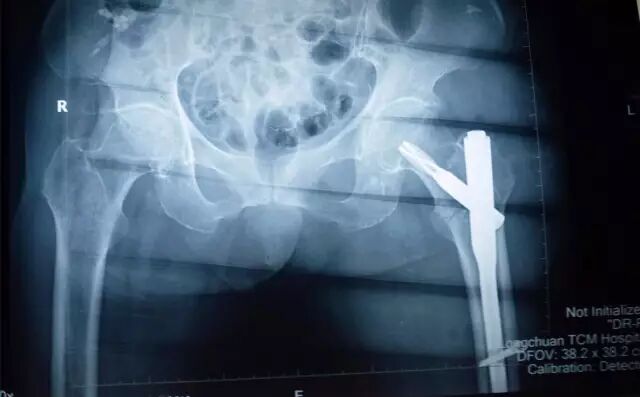

↑图:患者术后拍片情况